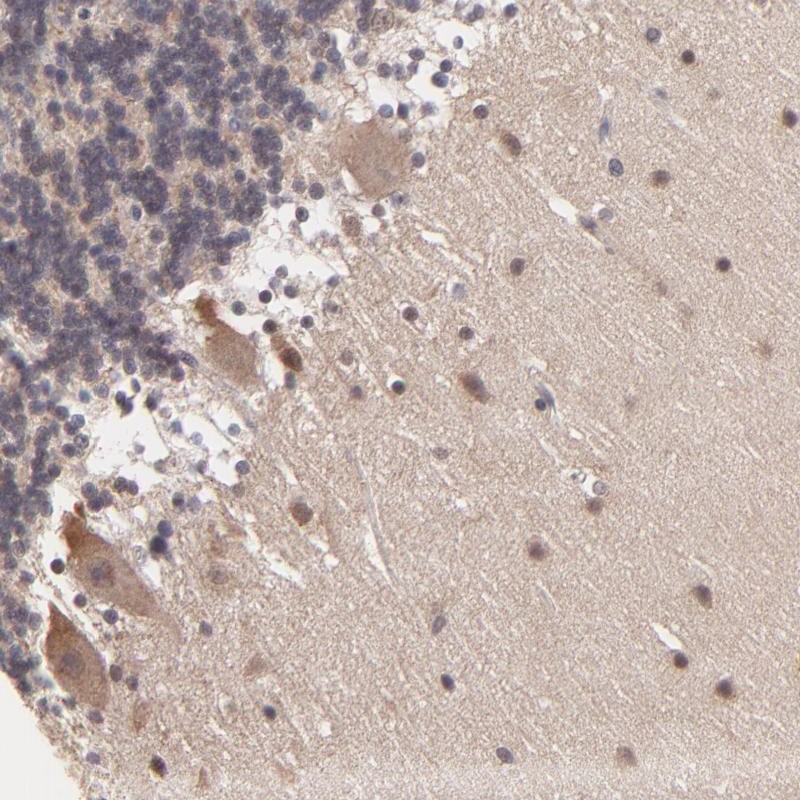

Immunohistochemical staining of human cerebellum shows cytoplasmic positivity in purkinje cells and nuclear immunoreactivity in cells of molecular layer.